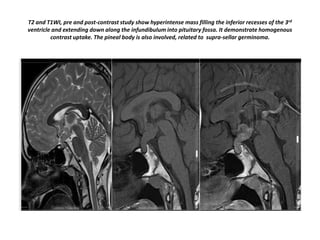

T2 and T1WI, pre and post-contrast study show hyperintense mass filling the inferior recesses of the 3rd

ventricle and extending down along the infundibulum into pituitary fossa. It demonstrate homogenous

contrast uptake. The pineal body is also involved, related to supra-sellar germinoma.